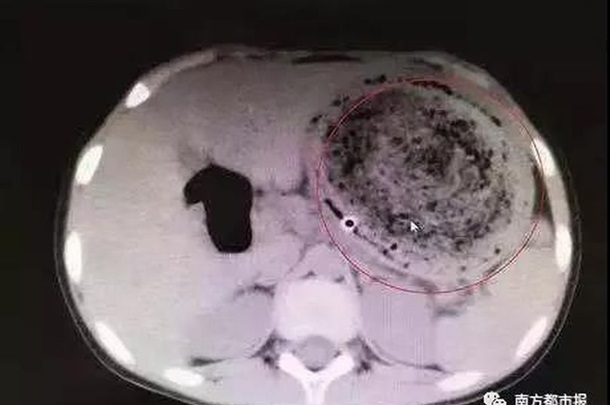

Когда промывание желудка не дало никакого результата, врачи сделали компьютерную томографию. На снимке специалисты обнаружили огромный комок волос с застрявшими в нем кусками еды.

Врачи сделали операцию и извлекли полуторакилограммовый комок волос. Сейчас девочка проходит послеоперационную реабилитацию.